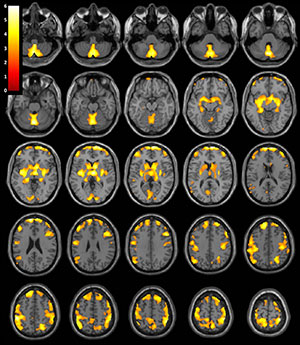

“We found that after an average of 13.5 months of abstinence, women who were previously dependent on stimulants had significantly less gray matter volume in several brain areas compared to healthy women,” said the study’s senior author, Jody Tanabe, M.D., professor of radiology, vice chair of Research, and Neuroradiology Section Chief at the University of Colorado Denver School of Medicine. “These brain areas are important for decision making, emotion, reward processing and habit formation.”

The researchers analyzed structural brain MRI exams in 127 men and women, including 59 people (28 women and 31 men) who were previously dependent on cocaine, amphetamines, and/or methamphetamine for an average of 15.7 years, and 68 healthy people (28 women and 40 men) who were similar in age and gender. The MRI results showed that after an average of 13.5 months of abstinence, women who were previously dependent on stimulants had significantly less gray matter volume in frontal, limbic and temporal regions of the brain.

“While the women previously dependent on stimulants demonstrated widespread brain differences when compared to their healthy control counterparts, the men demonstrated no significant brain differences,” Dr. Tanabe said.